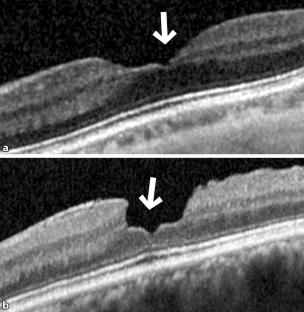

Abb. 1